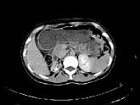

- 多项选择题女,35岁, 右侧腰部不适,CT增强扫描如图所示, 下列说法正确的是 ( )

A、右肾轮廓明显小于左侧,边缘光滑规则

B、左肾代偿性肥大

C、考虑为右小肾畸形

D、右肾完全无功能

E、考虑为右肾肾自截